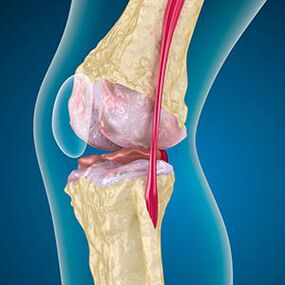

The knee joint arthrosis combines two processes: destruction of cartilage and grow osteophytes or bones.The process phase is determined by the radiograph.Arthrosis is believed to be destroying knee joints with age, the natural aging process.Causes are weakening muscles and poor blood supply in the tissue.How to treat yourself without surgery?Eliminate factors that reduced the muscle tone.

In addition to arthrosis, the lining of the cartilage of the edge of the bones are abrasion or completely absent.Damaged tissue is not a source of pain because there are no receptors.Inflammation in nearby structures causes characteristic symptoms.

The body continues the regeneration of damaged tissues, but the cartilage grows unevenly.As a result, irregularities that hurt other joint elements are formed.The nature of osteophytes is explained by a fee for the smooth wrist cartilage.The second version indicates the growth of "Spurs"It is associated with an attempt to jointly or laterally stabilize jointly or laterally due to muscle weakening.